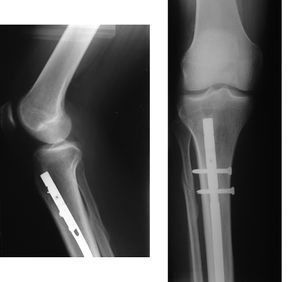

اكتشاف الكسور

ويستطيع الأطباء استكشاف الكسور بعدة طرق. فعادة يكون هناك ألم أو جرح، أو لين في منطقة الكسر. كما يكون هناك ورم في الأنسجةحول مكان الكسر وتغيُّر في اللون. وأحيانًا تتحرك العظمة تحت الجلد ويكون هناك تشوٌه ظاهر. ويدل صوت الطقطقة غالبًا على كسر في العظمة. والطقطقة صوت صرير خشن يحدث عندما تحتك نهايتا عظمة مكسورة بعضهما ببعض. ولكن هناك حالات لا يمكن فيها اكتشاف الكسر إلا باستخدام الأشعة السينية. وبصفة عامة،تلتئم الكسور البسيطة غير المصحوبة بخلع بسرعة،إذا تم تثبيتها في الجبس Plaster-of-Pairs أما الكسور المضاعفة والكسور المصحوبة بخلع، فتحتاج إلى علاج جراحي قبل وضع الجبس. ويجب أن يتوقف الجزء المكسور من الجسم عن الحركة حتى تتوفر المساعدة المتاحة.

- - تتوقف العملية الجراحية على نوع الكسر ، امكانيات الجراح العملية ، الامكانيات المتوفرة بحجرة العمليات .

- -العملية قد تكون بسيطة 1-2 براغي ،او DHS ، استبدال مفصل الورك THP .